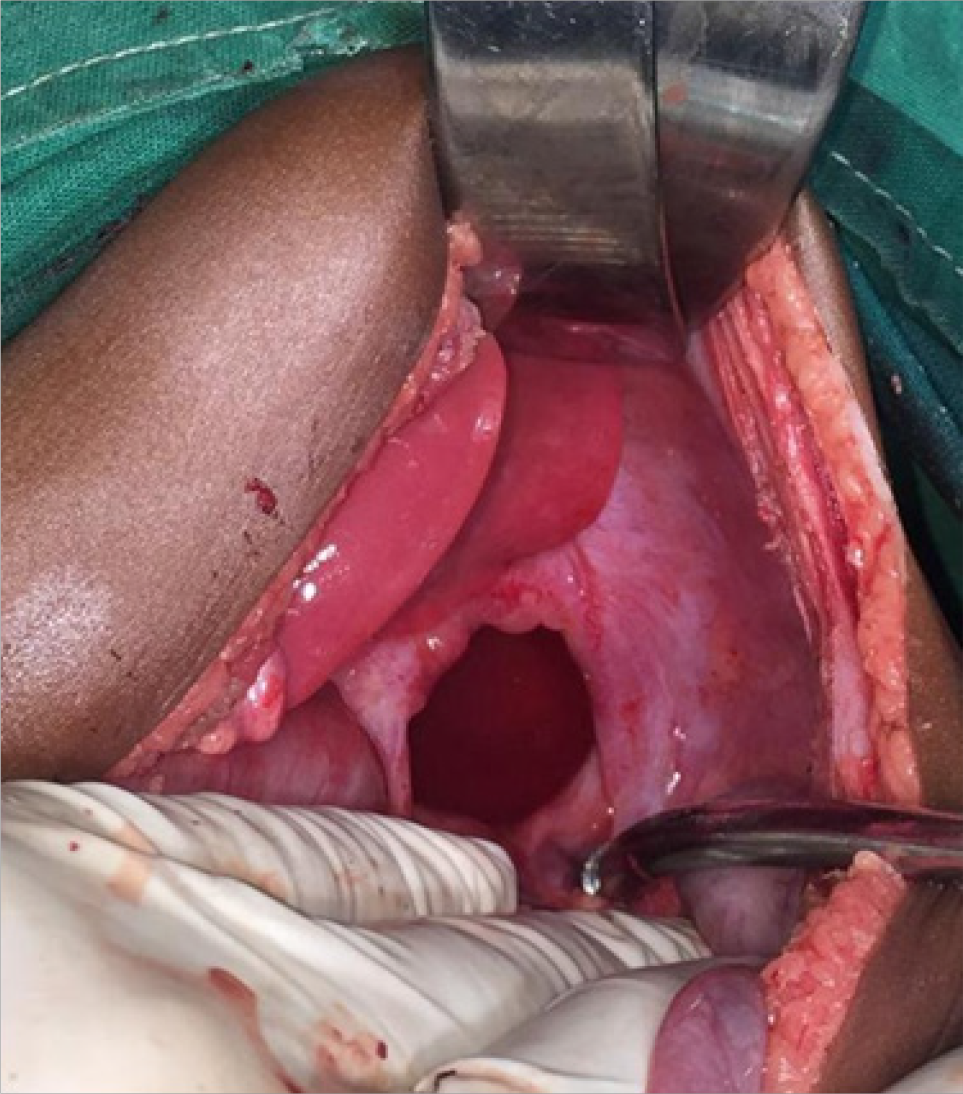

Methods: We present a six-month female baby who presented with clinical features of intestinal obstruction. Ultrasonography of the abdomen revealed gastric volvulus. The baby underwent emergency laparotomy. Gastric volvulus with splenic herniation was encountered through a diaphragmatic hernia.

Results: The defect was corrected, the stomach and spleen were mobilized into the normal anatomical position. The baby recovered well.